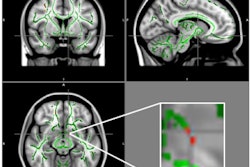

Image shows the neural pathways of the Tasmanian devil (left) and the thylacine, better known as the Tasmanian tiger. Image courtesy of Emory University.